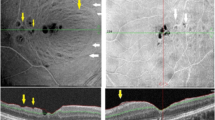

To quantitatively evaluate concentric macular dark spots (CMDS) on spectral-domain optical coherence tomography (SD-OCT) to determine the morphological characteristics of dissociated optic nerve fibre layer (DONFL) following the performance of internal limiting membrane (ILM) peeling in patients with full-thickness idiopathic macular hole (IMH) closure.

Retrospective study on patients who underwent a vitrectomy with ILM peeling procedure. BCVA, cross-sectional OCT scans, and three-dimensional reconstructions of en face OCT scans were analysed preoperatively, at 2, 6, 12 months post-operatively. A novel image analysis technique was used to automatically measure DONFL logical properties through the radius, area, the nerve fibre layer dissociation index (NFLDI), and depth of the CMDS.

53 eyes of 51 patients were included, and the mean follow-up was 11.53 ± 6.26 months. CMDS was found in 46 (86.79%) eyes within 2 months after ILM peeling and 50 (94.34%) eyes within 6 months after ILM peeling. CMDS concentrated on the temporal side of the macula in all 50 eyes (100%) at first detection. The area, NFLDI, and depth of CMDS in four quadrants developed significantly during the postoperative 6 months (p < 0.05), and then these changes slowed down and remained unchanged 12 months post-operatively. The morphological changes in the temporal quadrant were significantly greater than those in other quadrants at 2, 6, 12 months (all p < 0.05) post-operatively.

CMDS mostly appeared and concentrated on the temporal side of the macula in IMHs within two months after ILM peeling and progressed within 6 months and remained unchanged after 12 months.